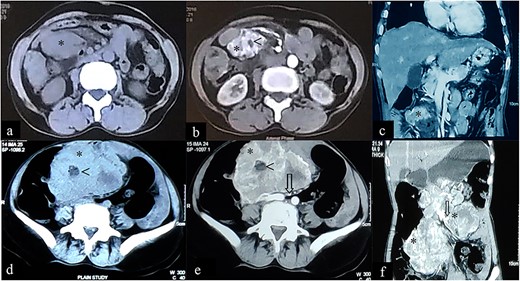

A 62-year-old female agricultural worker, presented with complaints of gradual abdominal distension over the past 2 years, associated with mild to moderate abdominal pain (exacerbated by meals), anorexia and gradual weight loss (~15-kg weight loss in 2 years). She was first seen at another hospital 18-month ago where contrast enhanced computed tomography (CECT) of abdomen revealed two heterogeneously enhancing exophytic lesions; one in the second part of the duodenum (43 mm × 36 mm) and the second in the right lumbar region (50 mm × 34 mm). The radiologic interpretation suggested EGIST (Fig. 1a–c), but the patient elected to not undergo any further workup or treatment.

Case 1: CT imaging of extragastrointestinal stromal tumor. (a) Non-contrast axial, (b, c) contrast enhanced axial and coronal reformatted CT images of abdomen demonstrate heterogeneously enhancing confluent mass (*) in peritoneal cavity anterior to the iliac vessels with central area of necrosis (<) peripherally displacing mesenteric vessels (arrow) and bowel. (d–f) Non-contrast axial, contrast enhanced axial and coronal reformatted CT images of abdomen of same patient after 1-year follow-up showing increased interval size of the lesion (*).

The patient presented to our outpatient clinic because of gradually worsening symptoms. She was alert and oriented with no acute distress and normal vital signs. With the exception of her abdominal examination, no abnormalities were detected. Her abdominal examination was remarkable for abdomen distension with burn scars on the anterior abdominal wall in the epigastric and left hypogastric region. There were no striae, dilated veins, rashes or visible peristalsis and bowel sounds were normal. The abdomen was soft with a large, firm and fixed mass (~15 cm × 15 cm) palpated in the epigastric/left hypochondriac region. Rectal examination was unremarkable. Laboratory studies included a complete blood count, renal function test, liver function test and a coagulation profile. All were normal. A repeat CECT of abdomen and pelvis showed: a large heterogeneously enhancing exophytic lesion (size ~18 cm) abutting the pancreatic head and superior mesenteric vessels, features suggestive of an EGIST (Fig. 1d–f).